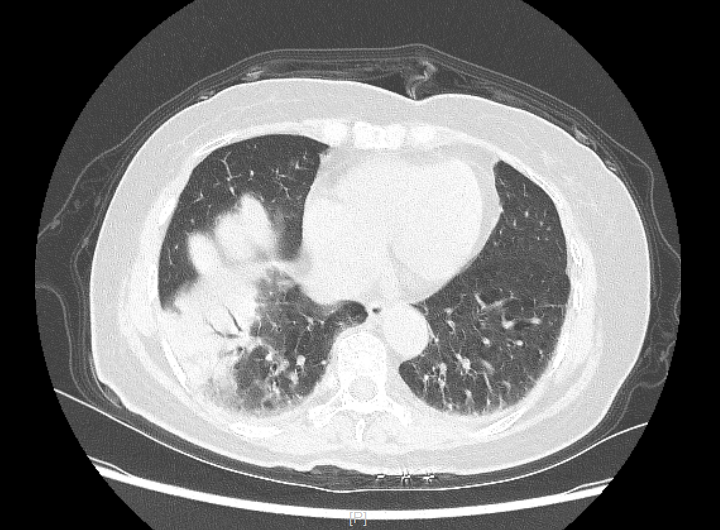

72岁的季阿姨平时身体一向健康,没有基础病,近期,突然出现发热,体温波动在39摄氏度左右,伴有些许咳嗽,本以为流感了,自行用了些感冒药,但无好转还出现了胸闷、呼吸不畅的症状,连夜来苏州高新区人民医院急诊就诊,肺CT检查显示:右肺大片实变影及渗出,伴有血炎症指标显著升高,后收住呼吸与危重症医学科治疗。第二天关键主任医师查房,询问病史了解到季阿姨家里有鹦鹉,结合患者血氧下降、凝血功能明显异常,关主任考虑存在鹦鹉热合并肺栓塞,在保证安全情况下完善了肺动脉CTA及支气管镜检查,行肺泡灌洗送基因检测,明确诊断为鹦鹉热合并肺栓塞、呼吸衰竭,后经过针对性治疗,季阿姨病情已明显好转,久违的笑容又回来了。